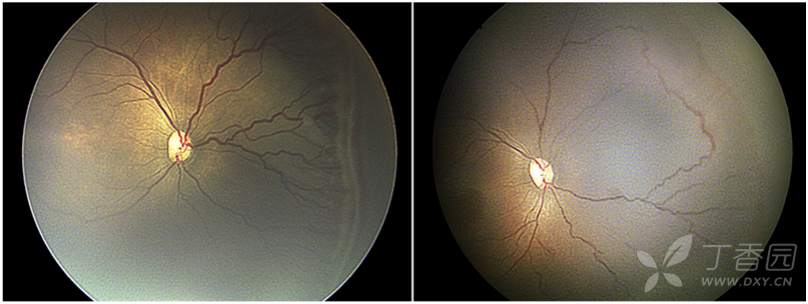

09、早产儿视网膜病变远期后遗症

图. 18岁患者既往有未经治疗的ROP病史,表现为牵引性和渗出性视网膜脱离。

图. 7岁患儿有自发消退ROP病史,超广角FA可见持续性视网膜无血管区(星号),颞下方异常的血管结构(圆圈)。

图. 7岁患儿有自发消退ROP病史,超广角FA可见颞下方不完全消退的3期病变处存在持续性视网膜无血管区和渗漏(星号)。

图. 15岁患儿有极度早产史,之前无ROP治疗史,超广角眼底图像(左侧)可见不完全消退的与持续性视网膜无血管区(星号)。2年后(右侧)患者出现累及黄斑部的孔源性